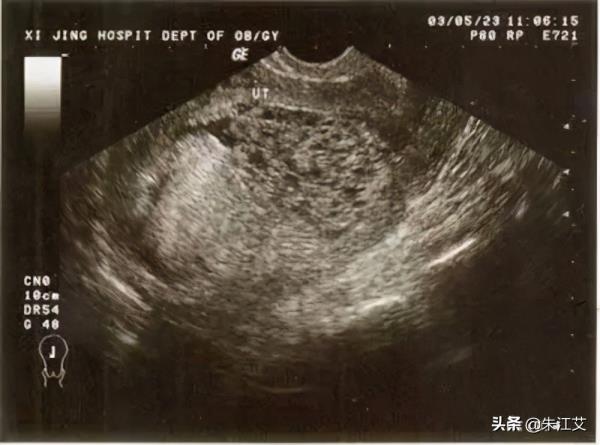

一般宫外孕出血的情况都伴随着严重的腹痛。在怀孕6周左右可以通过B超检查,排除异位妊娠的情况

2)如果是部分性葡萄胎一般怀孕50天以上能查出,完全性葡萄胎怀孕44天左右结合彩超,HCG情况能判断出。